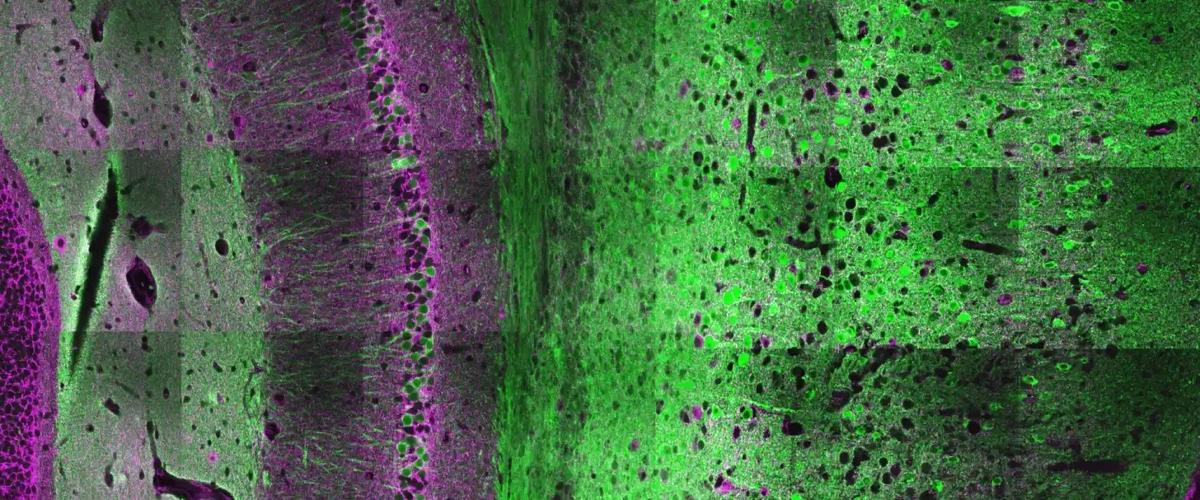

Исследователи из Университета Джона Хопкинса изучали рецепторы AMPA, которые имеют решающее значение для быстрой передачи информации и формирования памяти. Ученые искали механизмы, которые контролируют специфичность реакции нейронов на внешние сигналы, чтобы разобраться в природе многих психических нарушений.

Оказалось, что управляет процессом молекула (CP)-AMPA, находящаяся на поверхности клеток мозга, сообщается на сайте университета. Эксперименты показали, что молекула может подавлять способность определенной группы нейронов реагировать на сигналы.

Дальнейшие наблюдения выявили связь белковой мутации GluA2 в рецепторе AMPA с развитием умственных нарушений. В дальнейшем ученые планируют изучить все потенциальные молекулы и механизмы, связанные с (CP)-AMPA, которые участвуют в развитии расстройства аутистического спектра, шизофрении, эпилепсии и других заболеваний. В случае успеха результаты приведут к появлению целевых лекарств для этих диагнозов.